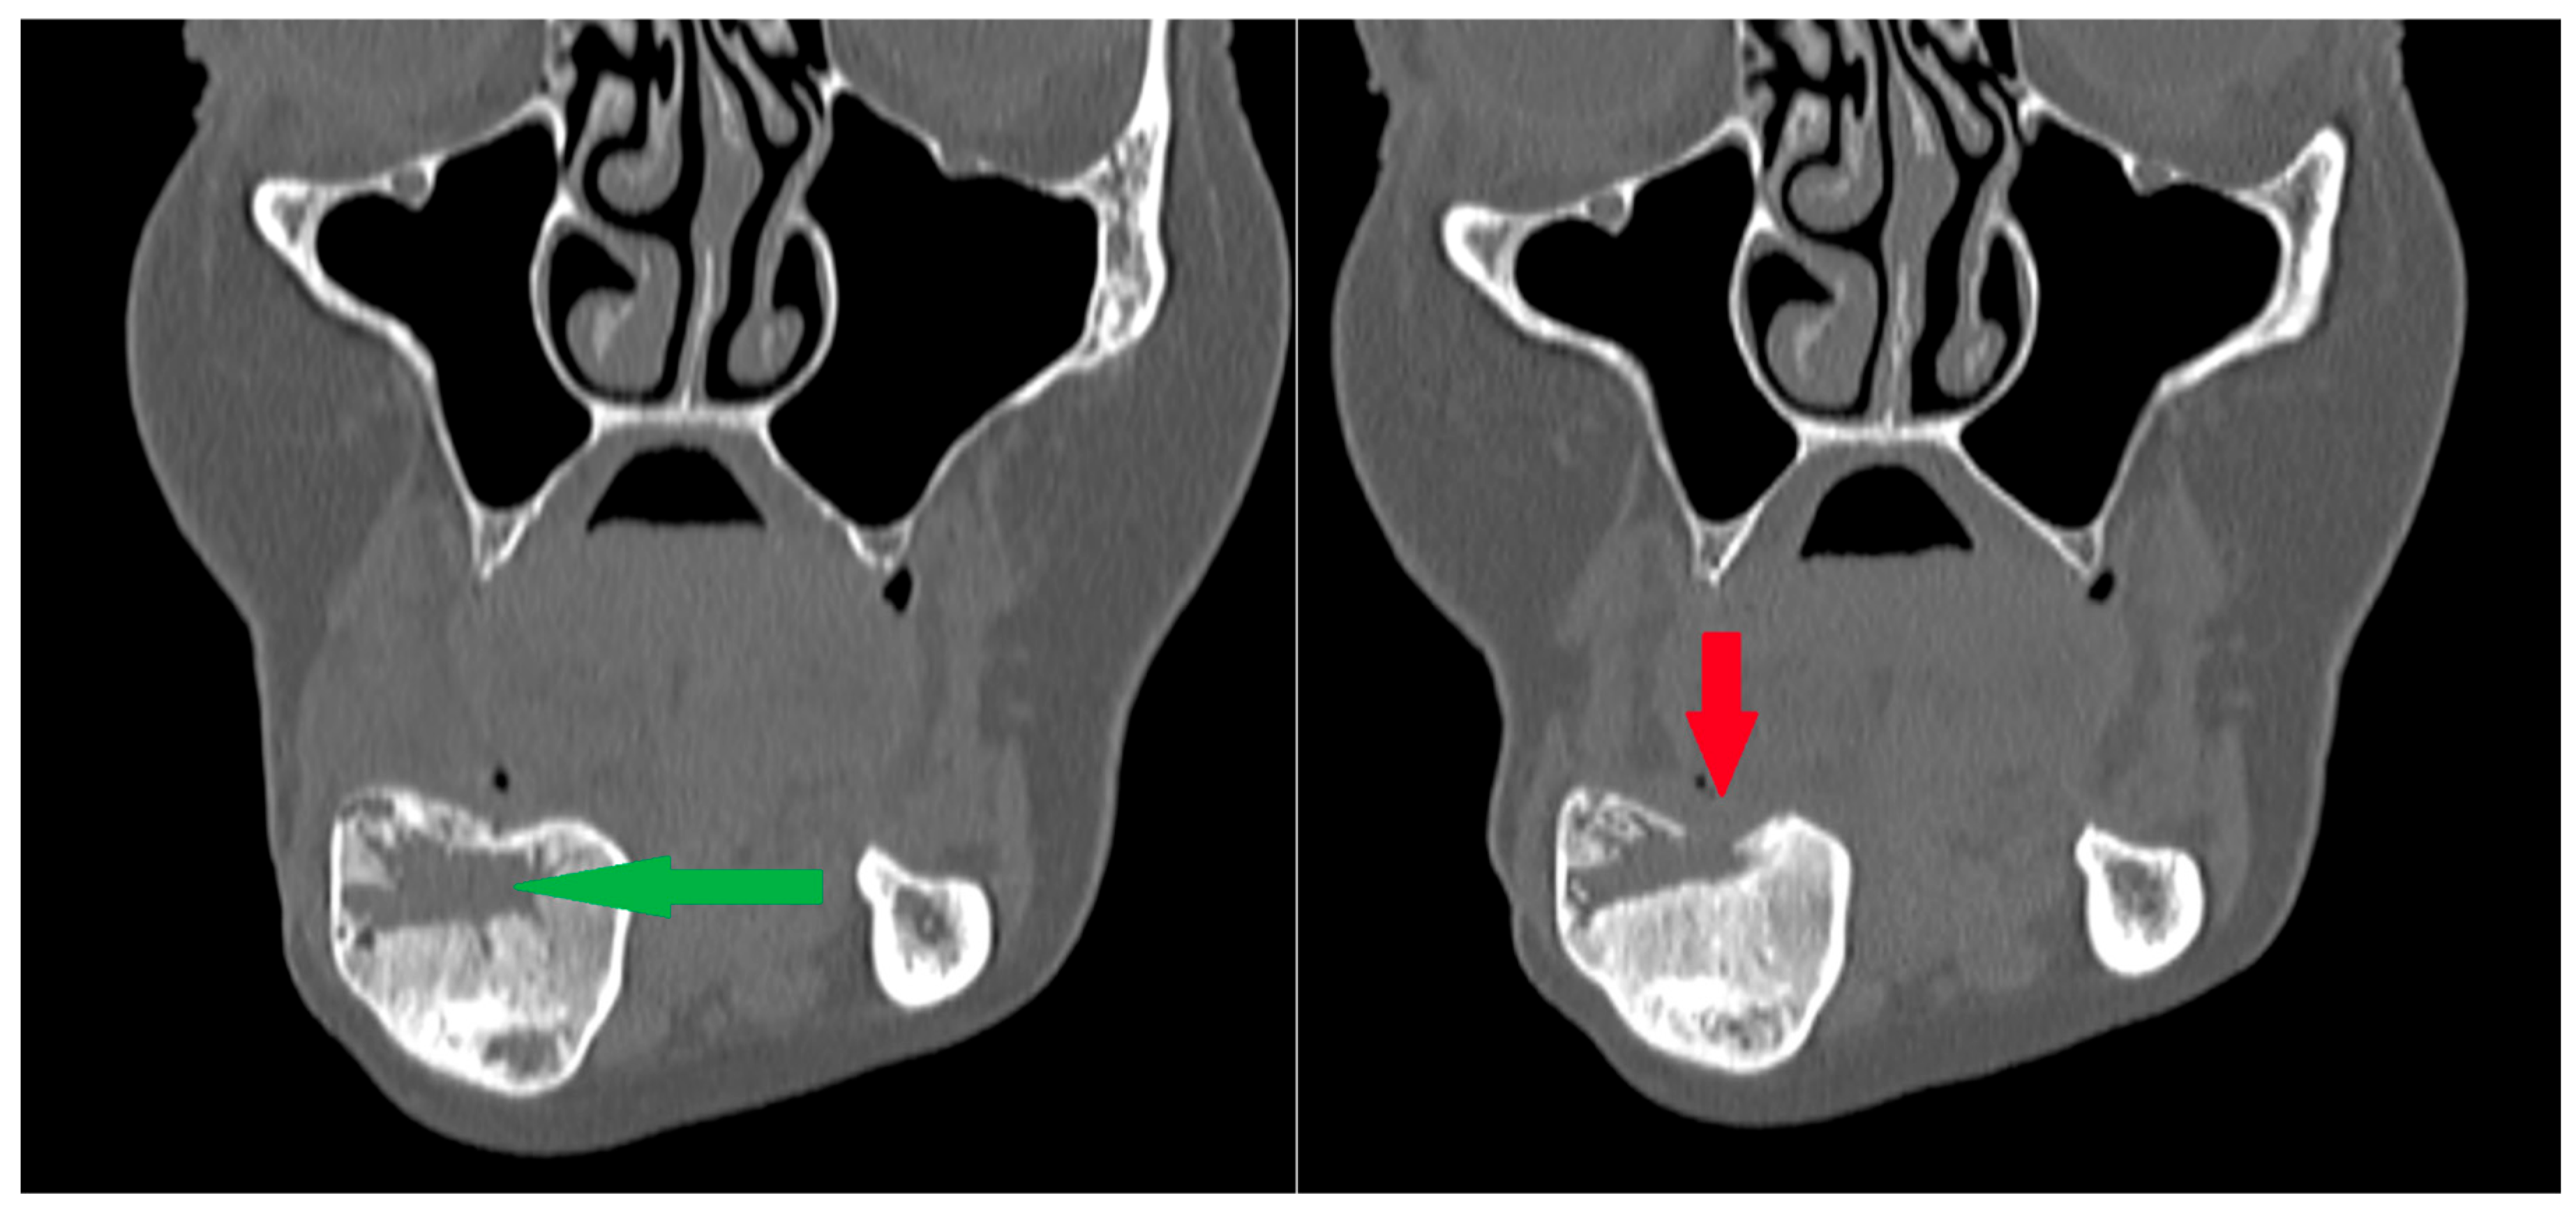

3.3. Osteosclerotic Rim (Peripheral Corticalization)